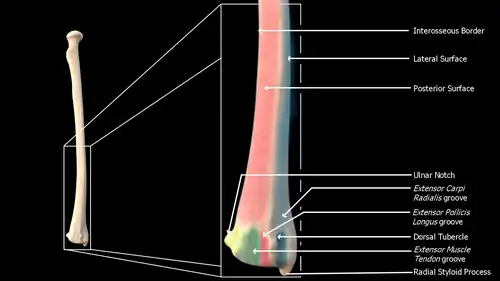

Near the wrist

The distal end of the radius is large and of quadrilateral form.

- Joint surfaces

It is provided with two articular surfaces – one below, for the carpus, and another at the medial side, for the ulna.

- The carpal articular surface is triangular, concave, smooth, and divided by a slight antero-posterior ridge into two parts. Of these, the lateral, triangular, articulates with the scaphoid bone; the medial, quadrilateral, with the lunate bone.

- The articular surface for the ulna is called the ulnar notch (sigmoid cavity) of the radius; it is narrow, concave, smooth, and articulates with the head of the ulna.

These two articular surfaces are separated by a prominent ridge, to which the base of the triangular articular disk is attached; this disk separates the wrist-joint from the distal radioulnar articulation.

- Other surfaces

This end of the bone has three non-articular surfaces – volar, dorsal, and lateral.

- The dorsal surface is convex, affords attachment to the dorsal radiocarpal ligament, and is marked by three grooves. Enumerated from the lateral side:

- The first groove is broad, but shallow, and subdivided into two by a slight ridge: the lateral of these two, transmits the tendon of the extensor carpi radialis longus muscle; the medial, the tendon of the extensor carpi radialis brevis muscle.

- The second is deep but narrow, and bounded laterally by a sharply defined ridge; it is directed obliquely from above downward and lateralward, and transmits the tendon of the extensor pollicis longus muscle.

- The third is broad, for the passage of the tendons of the extensor indicis proprius and extensor digitorum communis.

- The lateral surface is prolonged obliquely downward into a strong, conical projection, the styloid process, which gives attachment by its base to the tendon of the brachioradialis, and by its apex to the radial collateral ligament of wrist joint. The lateral surface of this process is marked by a flat groove, for the tendons of the abductor pollicis longus muscle and extensor pollicis brevis muscle.

The dorsal surface (facies dorsalis; posterior surface) is convex, and smooth in the upper third of its extent, and covered by the Supinator. Its middle third is broad, slightly concave, and gives origin to the Abductor pollicis longus above, and the extensor pollicis brevis muscle below. Its lower third is broad, convex, and covered by the tendons of the muscles which subsequently run in the grooves on the lower end of the bone.

Posterior view of right distal radius

Posterior view of right distal radius -